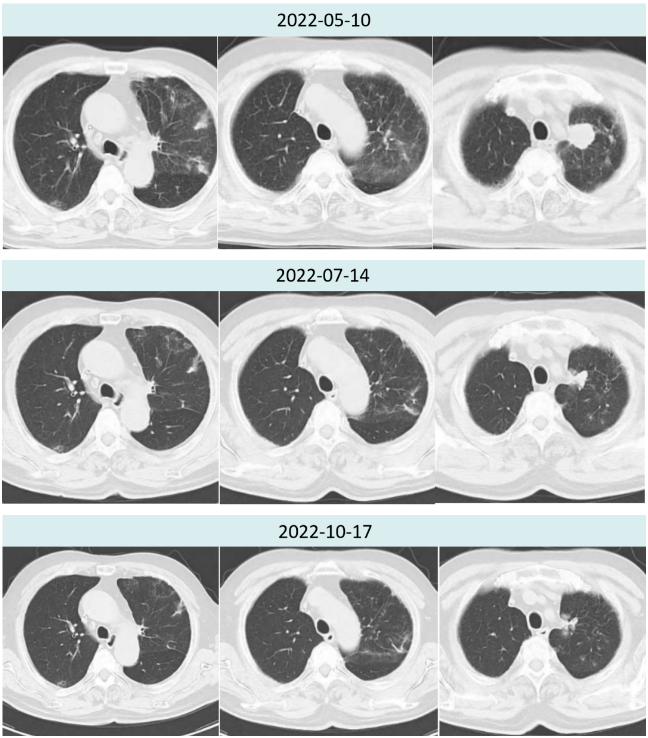

2022年6月1日开始给予患者斯鲁利单抗200mg q3w+安罗替尼10mg d1-14 q3w治疗。

2022年7月14日斯鲁利单抗联合安罗替尼治疗两周期后,胸部CT提示肿瘤病灶较前再次缩小,疗效评价PR(2.9cm→1.6cm),且两肺间质性炎症较前好转。

2022年10月17日斯鲁利单抗联合安罗替尼治疗六周期后,胸部CT提示肿瘤病灶较前继续缩小,疗效评价持续PR(2.9cm→1.4cm)。

图3.患者治疗前后胸部病灶及肺炎情况对比